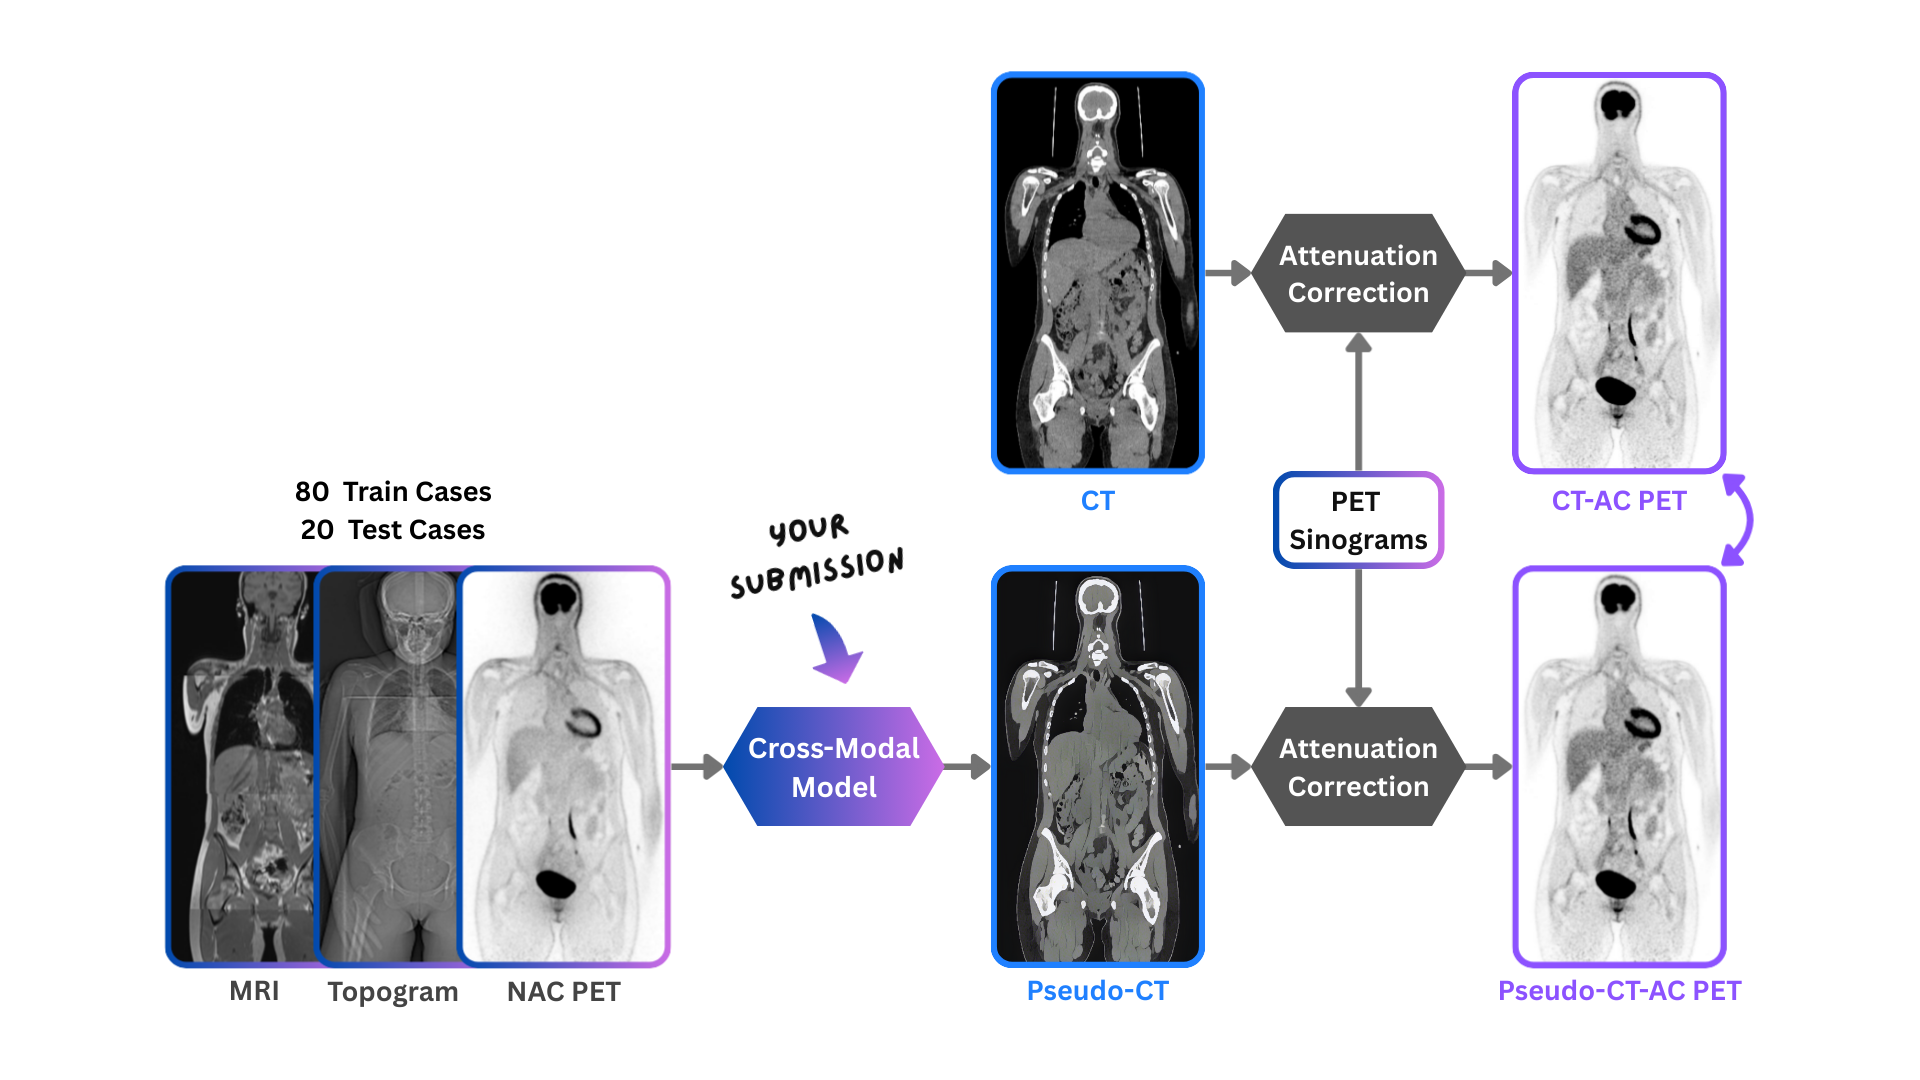

To address this, the Big Cross-Modal Attenuation Correction (BIC-MAC) challenge tasks participants with

synthesizing a 3D pseudo-CT from other available modalities. We present a novel multimodal dataset comprising

whole-body PET, CT, Topogram (scout radiograph), and MRI for 99 healthy volunteers. The cohort is age- and

sex-stratified, with data acquired on Siemens Biograph Vision Quadra and Siemens MAGNETOM Vida

scanners. Participants will receive a training set of 75 cases containing Non-Attenuation Corrected (NAC)

[18F]FDG PET images, scan-planning Topograms, and same-day DIXON MRI, alongside reference CT and CT-based attenuation-corrected PET (CTAC-PET) images. Critically, we also provide scatter maps, sinograms, and

Docker containers with open-source reconstruction software, enabling closed-loop optimization on the training

set - a capability previously restricted to hospital sites with access to proprietary vendor software.

The challenge comprises a single task: generate a pseudo-CT from the available input modalities. The pseudo-CT will be used to reconstruct PET images, which are then quantitatively compared against reference CTAC-PET images. Both static and dynamic PET reconstructions are evaluated to assess downstream accuracy across

different clinical contexts. A defining technical characteristic of this challenge is the integration of modalities with

different dimensionalities and acquisition geometries. While the 3D NAC-PET and 2D Topograms are spatially

aligned with the target attenuation map, both lack anatomical detail. In contrast, whole-body MRI offers high

bone and soft-tissue contrast but is acquired in a different scanner geometry with different patient positioning

and body deformations. Consequently, participants must develop algorithms capable of fusing spatially

unaligned information from 3D volumetric MRI with that of the 3D NAC-PET and 2D Topograms.